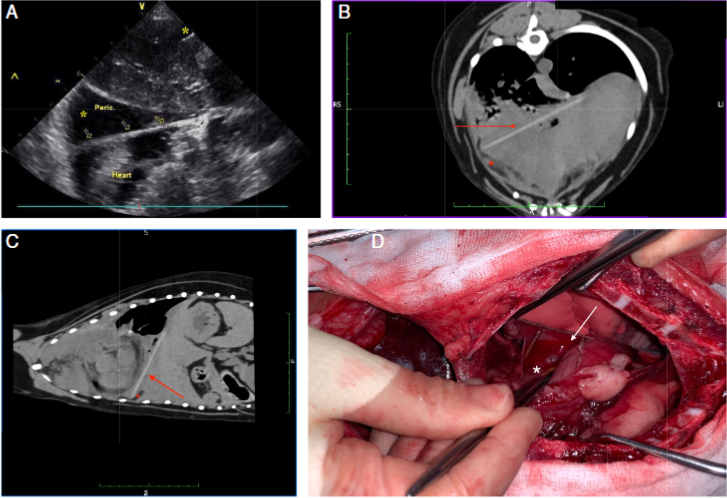

방사선 검사에서 나무는 보이지 않는게 정상이고

CT 정도를 찍어야 나온다.

물론 초음파 검사에서 대부분 잘 나오지만

주변으로 염증이 너무 심한 경우에는 오히려 환자가 통증을 호소하여 검사에 장애가 있어 놓치는 경우가 더러 생긴다.